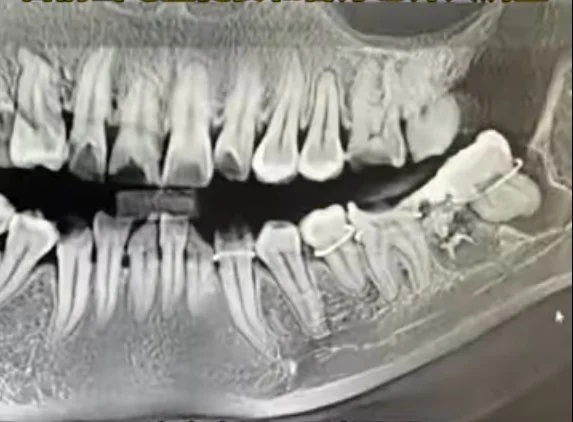

综合媒体报导,家属透露,吴女士12日在安庆市立医院拔智齿,被拔错了一颗原生牙齿,随后医师又把拔下的这颗牙硬塞了回去,“医师用铁丝把几颗牙捆住串起来,这一个半小时没有打麻药”,导致其牙齿损坏,面部肿胀,晚上疼得睡不着。

吴女士哥哥表示,院方还擅自修改妹妹病历,“我妹妹当时不知道,后来去别的医院拍片后才知道那个医师搞得有多离谱。”因当时打麻醉是打在智齿部位,原生好牙的位置并未麻醉,医师是“硬生生拔下来的”。